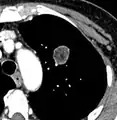

Round well-delineated solid lung nodule with smooth border.[9]